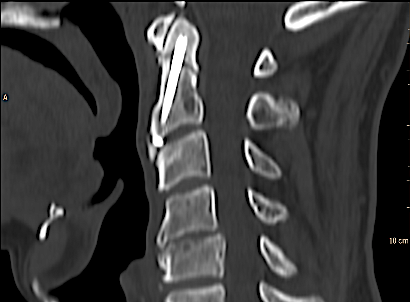

En este caso se decidió atornillado anterior (técnica de Apfelbaum) con un solo tornillo (el cuello estrecho de la odontoides nos planteó dudas para ubicar dos). El paciente mejoró en el postoperatorio inmediato, sin presentar complicaciones ni secuelas.

TC sagital control al año de la intervención. Paciente asintomático.